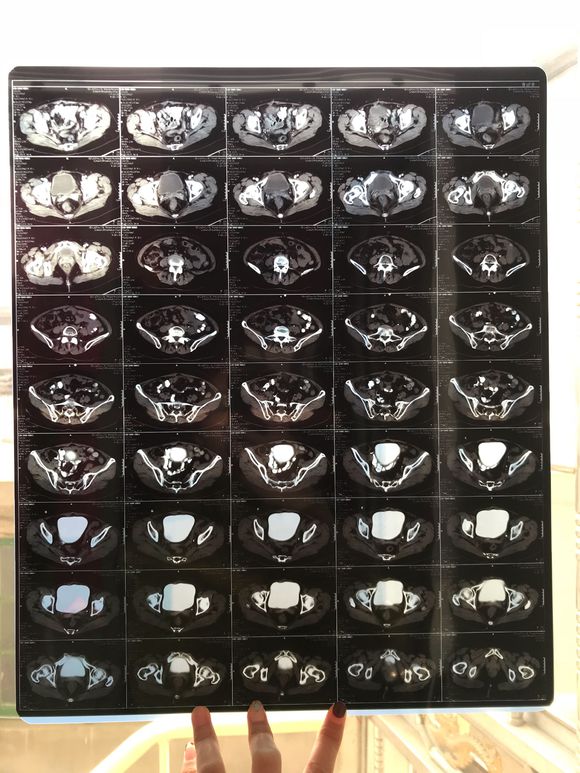

和你的故事 02019-04-09 患者家属我妈妈的病理结果报告,3期c1,大家可以帮忙看看吗,跪求了!我很急,谢谢!想知道是否严重,目前等术后出院后去肿瘤医院...

0人关注 4个回复 3530次浏览 -